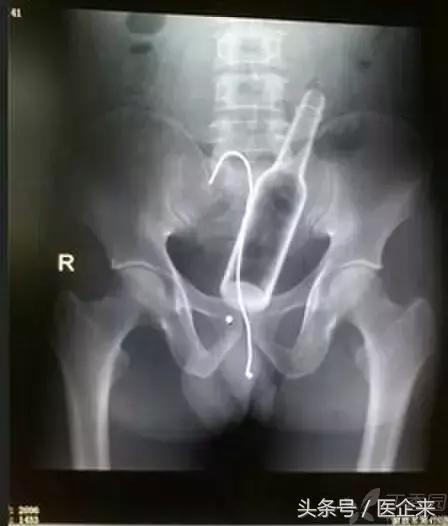

8. 啤酒瓶,还有个铁丝钩(想用铁丝勾出来?然鹅...)